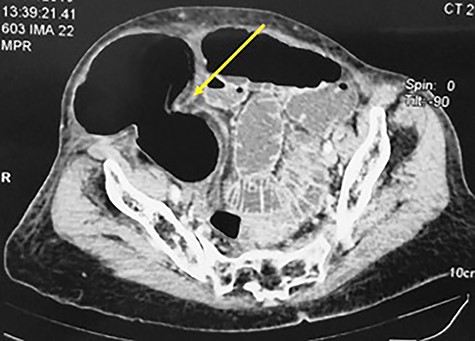

An 84-year-old patient, gravida 8, para 8, consulted in emergency department for abdominal pain and vomiting evolving for 7 days. The blood pressure was 120/70 mm Hg with a fever at 38.6°. The physical examination found an ovoid non-reducible mass of the right lower quadrant (Fig. 1). There was no abdominal tenderness or peritoneal signs. The computed tomography (CT) scan showed a strangulated right spigelian hernia with a hernial ring measured to 3.4 cm. The content was the coecum (Fig. 2). There were also signs of bowel ischemia with pneumatosis and minimal peritoneal effusion (Fig. 3). Biology found leukocytosis at 15 200 elements per mm3. Surgical exploration with an incision centered on the mass confirmed the diagnosis. There was an extensive necrosis of the hernial sac and its contents (the caecum, appendix and 10 cm of the terminal ileum) (Figs 4 and 5). A right hemi-colectomy with an ileo-colic anastomosis was performed. The parietal defect was closed by an aponeurorraphy with Mersuture 0. The post-operative course was marked by the death of the patient in intensive care due to multi-visceral failure.

Abdominal CT scan showing a strangulated right spigelian hernia with pneumatosis (arrow).